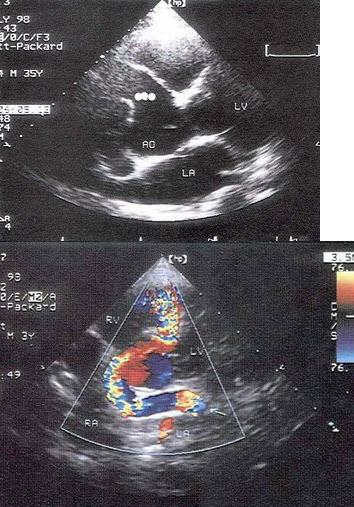

30、单项选择题

根据心尖四腔切面声像图所示,超声诊断为()

A.右房血栓

B.三尖瓣赘生物

C.右房黏液瘤

D.正常声像图

E.二尖瓣脱垂